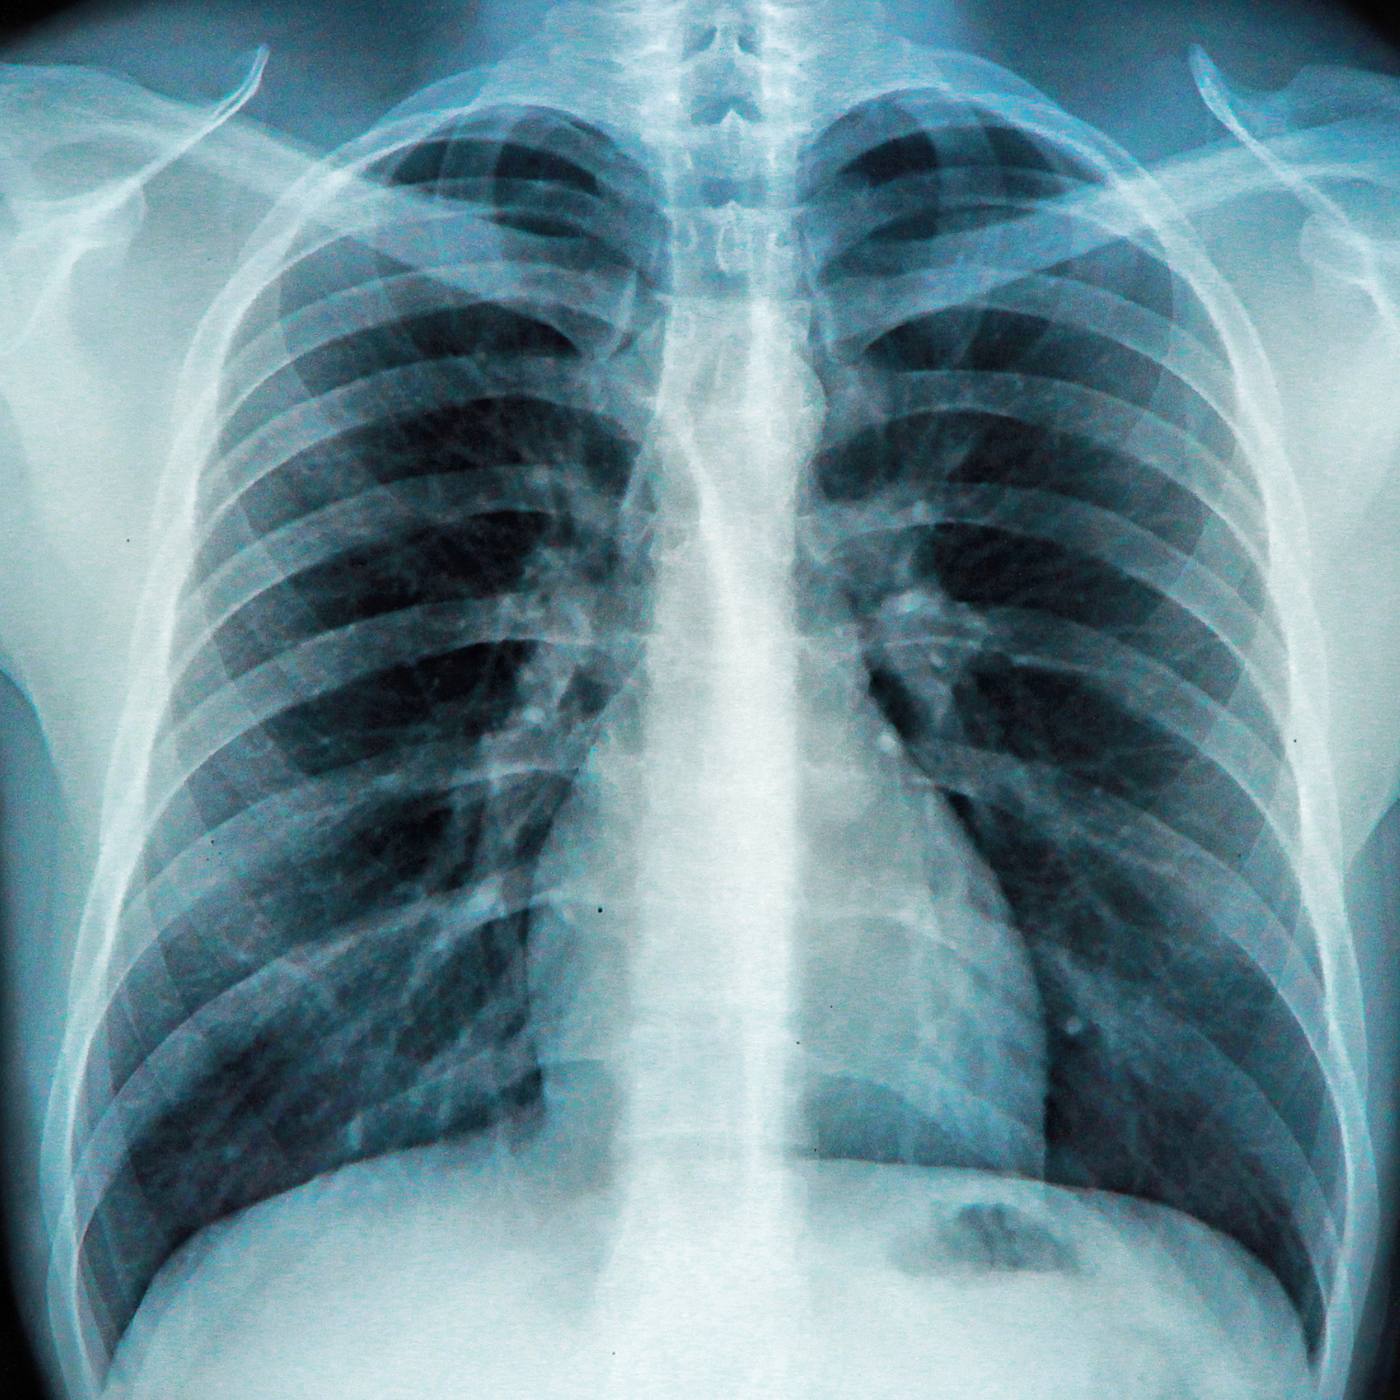

X-Ray

Accidents can occur at anytime and for any fall related accidents the need for an X-Ray service that is available 24 hours is absolutely crucial so we realized the need and made it available for the people of the city. CHRC happily provides X-Ray services as a 24/7 service of their clinic. We are always there because we care.